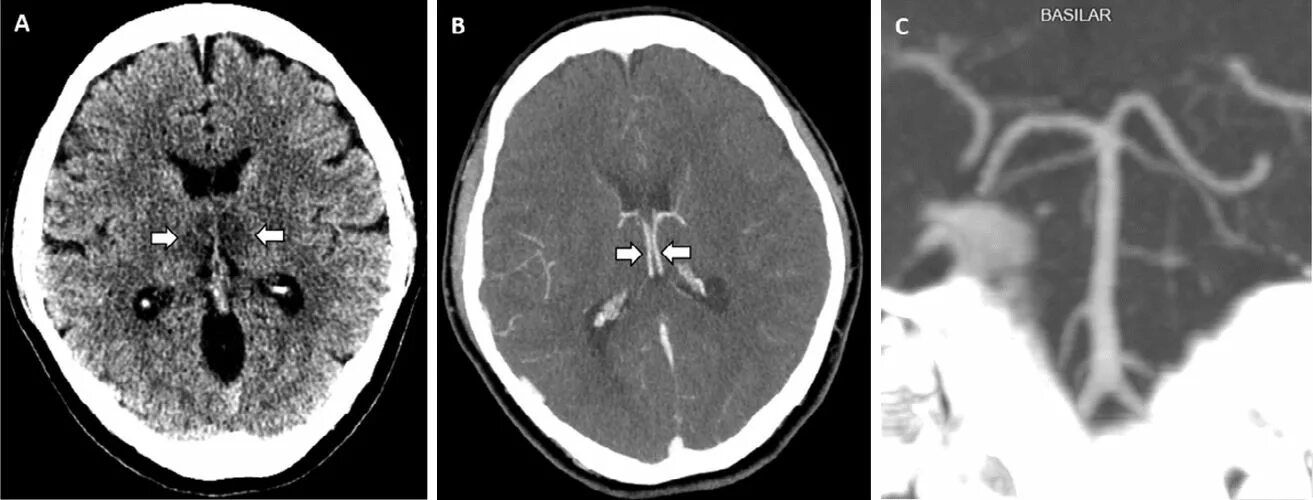

Микроангиопатия головного мозга симптомы